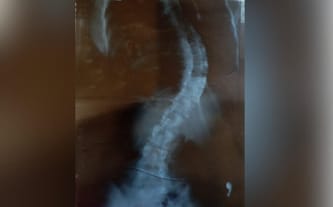

Ogromna skolioza utrudnia oddychanie❗️Oliwia natychmiast potrzebuje operacji!

Skolioza wciąż postępuje, utrudnia najprostsze codzienne czynności. Teraz stan Oliwki jest tragiczny. Z dnia na dzień jest coraz gorzej! Oliwia miała 11 lat, kiedy stwierdzono u niej wadę kręgosłupa. Wraz z wiekiem jej stan znacznie się pogarszał. Odkąd córka ukończyła 13 lat, jej walka o sprawność toczy się z podwójną mocą...

Niestety, okazało się, że to za mało. Skolioza w dramatycznym tempie przyspieszyła swój rozwój! Córka ma ogromne problemy z chodzeniem i oddychaniem. Choć wciąż porusza się samodzielnie, nie może zbyt długo tego robić. Szybko się męczy, opada z sił. Wejście na schody jest dla niej niesamowitym wysiłkiem, a każdy ruch – ogromnym bólem.

Ponadto krzywizna uciska na narządy wewnętrzne, zwłaszcza na płuca. To sprawia, że Oliwia ma poważne trudności z oddychaniem! Gdy złapie ją lekkie przeziębienie, jest chora przez kilka miesięcy. Nie może dojść do siebie ze względu na słabą wentylację płuc.

Operacja kręgosłupa to nasza OSTATNIA NADZIEJA na sprawność. W styczniu byliśmy na konsultacji u doktora, który ma przeprowadzić zabieg. To konieczne, aby odbył się jak najszybciej, ponieważ stan zdrowia Oliwii będzie tylko się pogarszał, a przecież już jest tragicznie! Lekarze zapewnili nas, że gdy tylko uzbieramy wymaganą kwotę, zabieg zostanie przeprowadzony w najbliższym możliwym terminie. To jedyna szansa na odzyskanie sprawności, na samodzielne funkcjonowanie i ulgę w tak obezwładniającym bólu.